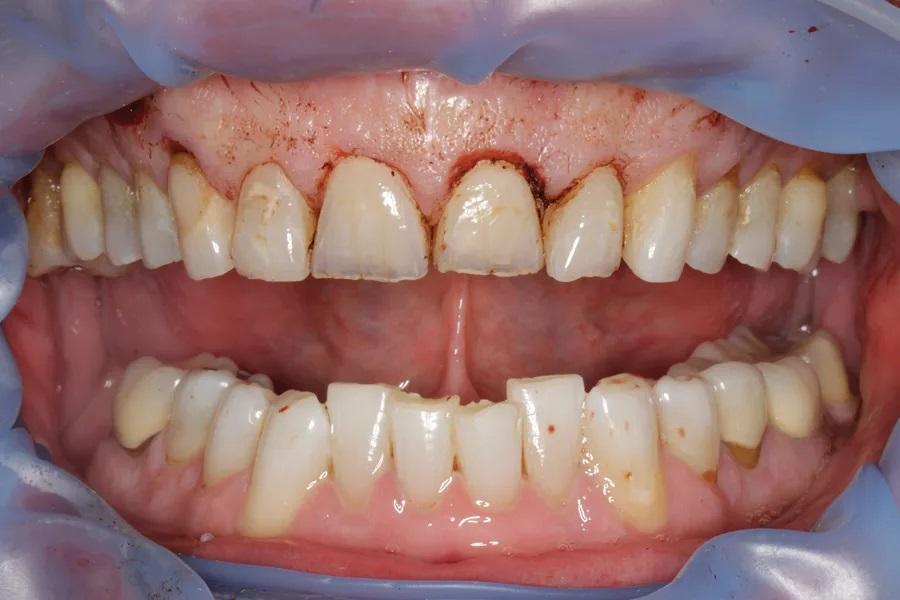

Мужчина, 45 лет. Основная жалоба — неловкость при улыбке из-за коротких, деформированных и измененных в цвете зубов. Обследование выявило гингивит с соответствующей потерей прикрепления, множественные кариозные поражения, износ зубов и реставраций (Фото 1 – Фото 3). Зафиксирован ограниченный паттерн жевания (ОПЖ), что определило умеренный функциональный риск и необходимость учета окклюзии в плане лечения.

Фото 3. Вид с ретракторами до лечения. Износ, истончение эмали, окрашивание зубов.